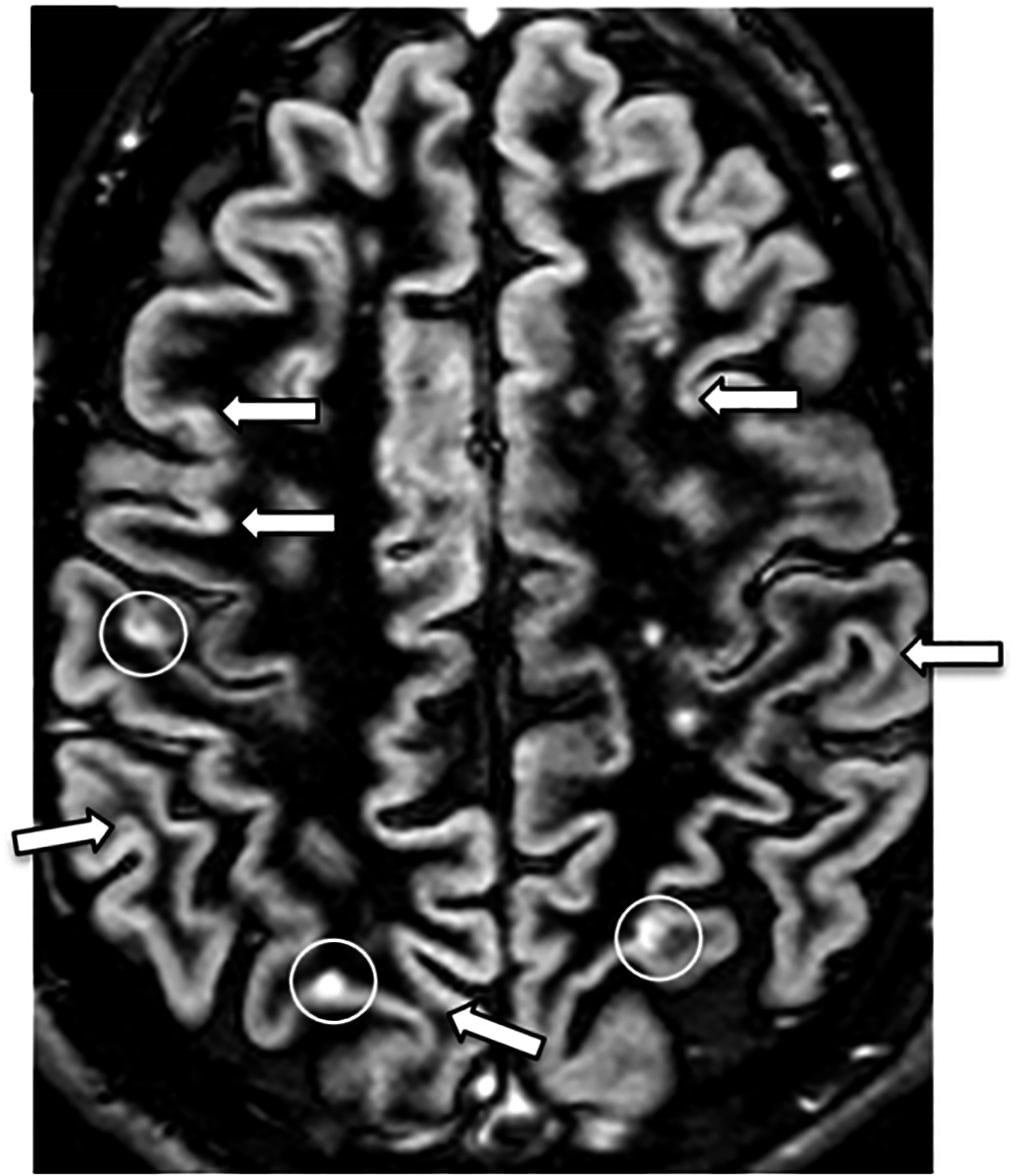

MRT skaneeringut kasutatakse väga erinevate haiguste diagnoosimiseks. Sellel pildil on näha polüskleroosi kolded.